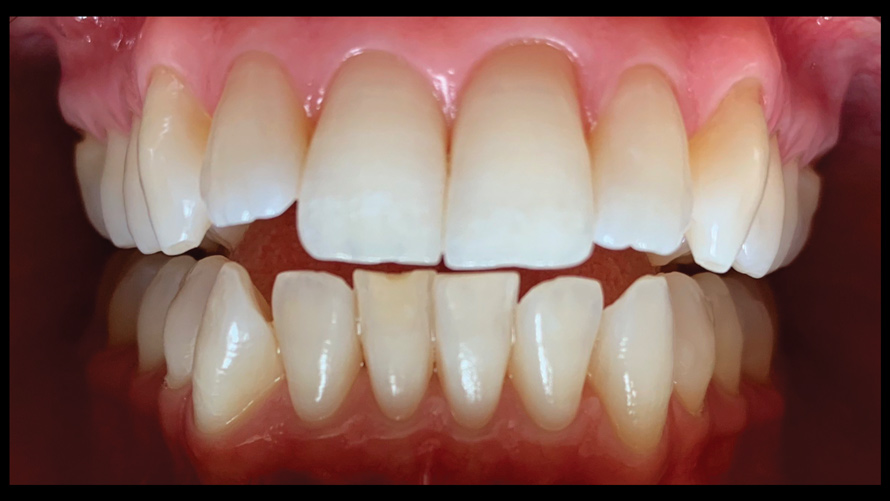

(9.) Preoperative esthetic case documentation using a smartphone and an EALS device.

Figure 9

(10.) Preoperative esthetic case documentation using a smartphone and an EALS device.

Figure 10

(11.) Preoperative esthetic case documentation using a smartphone and an EALS device.

Figure 11